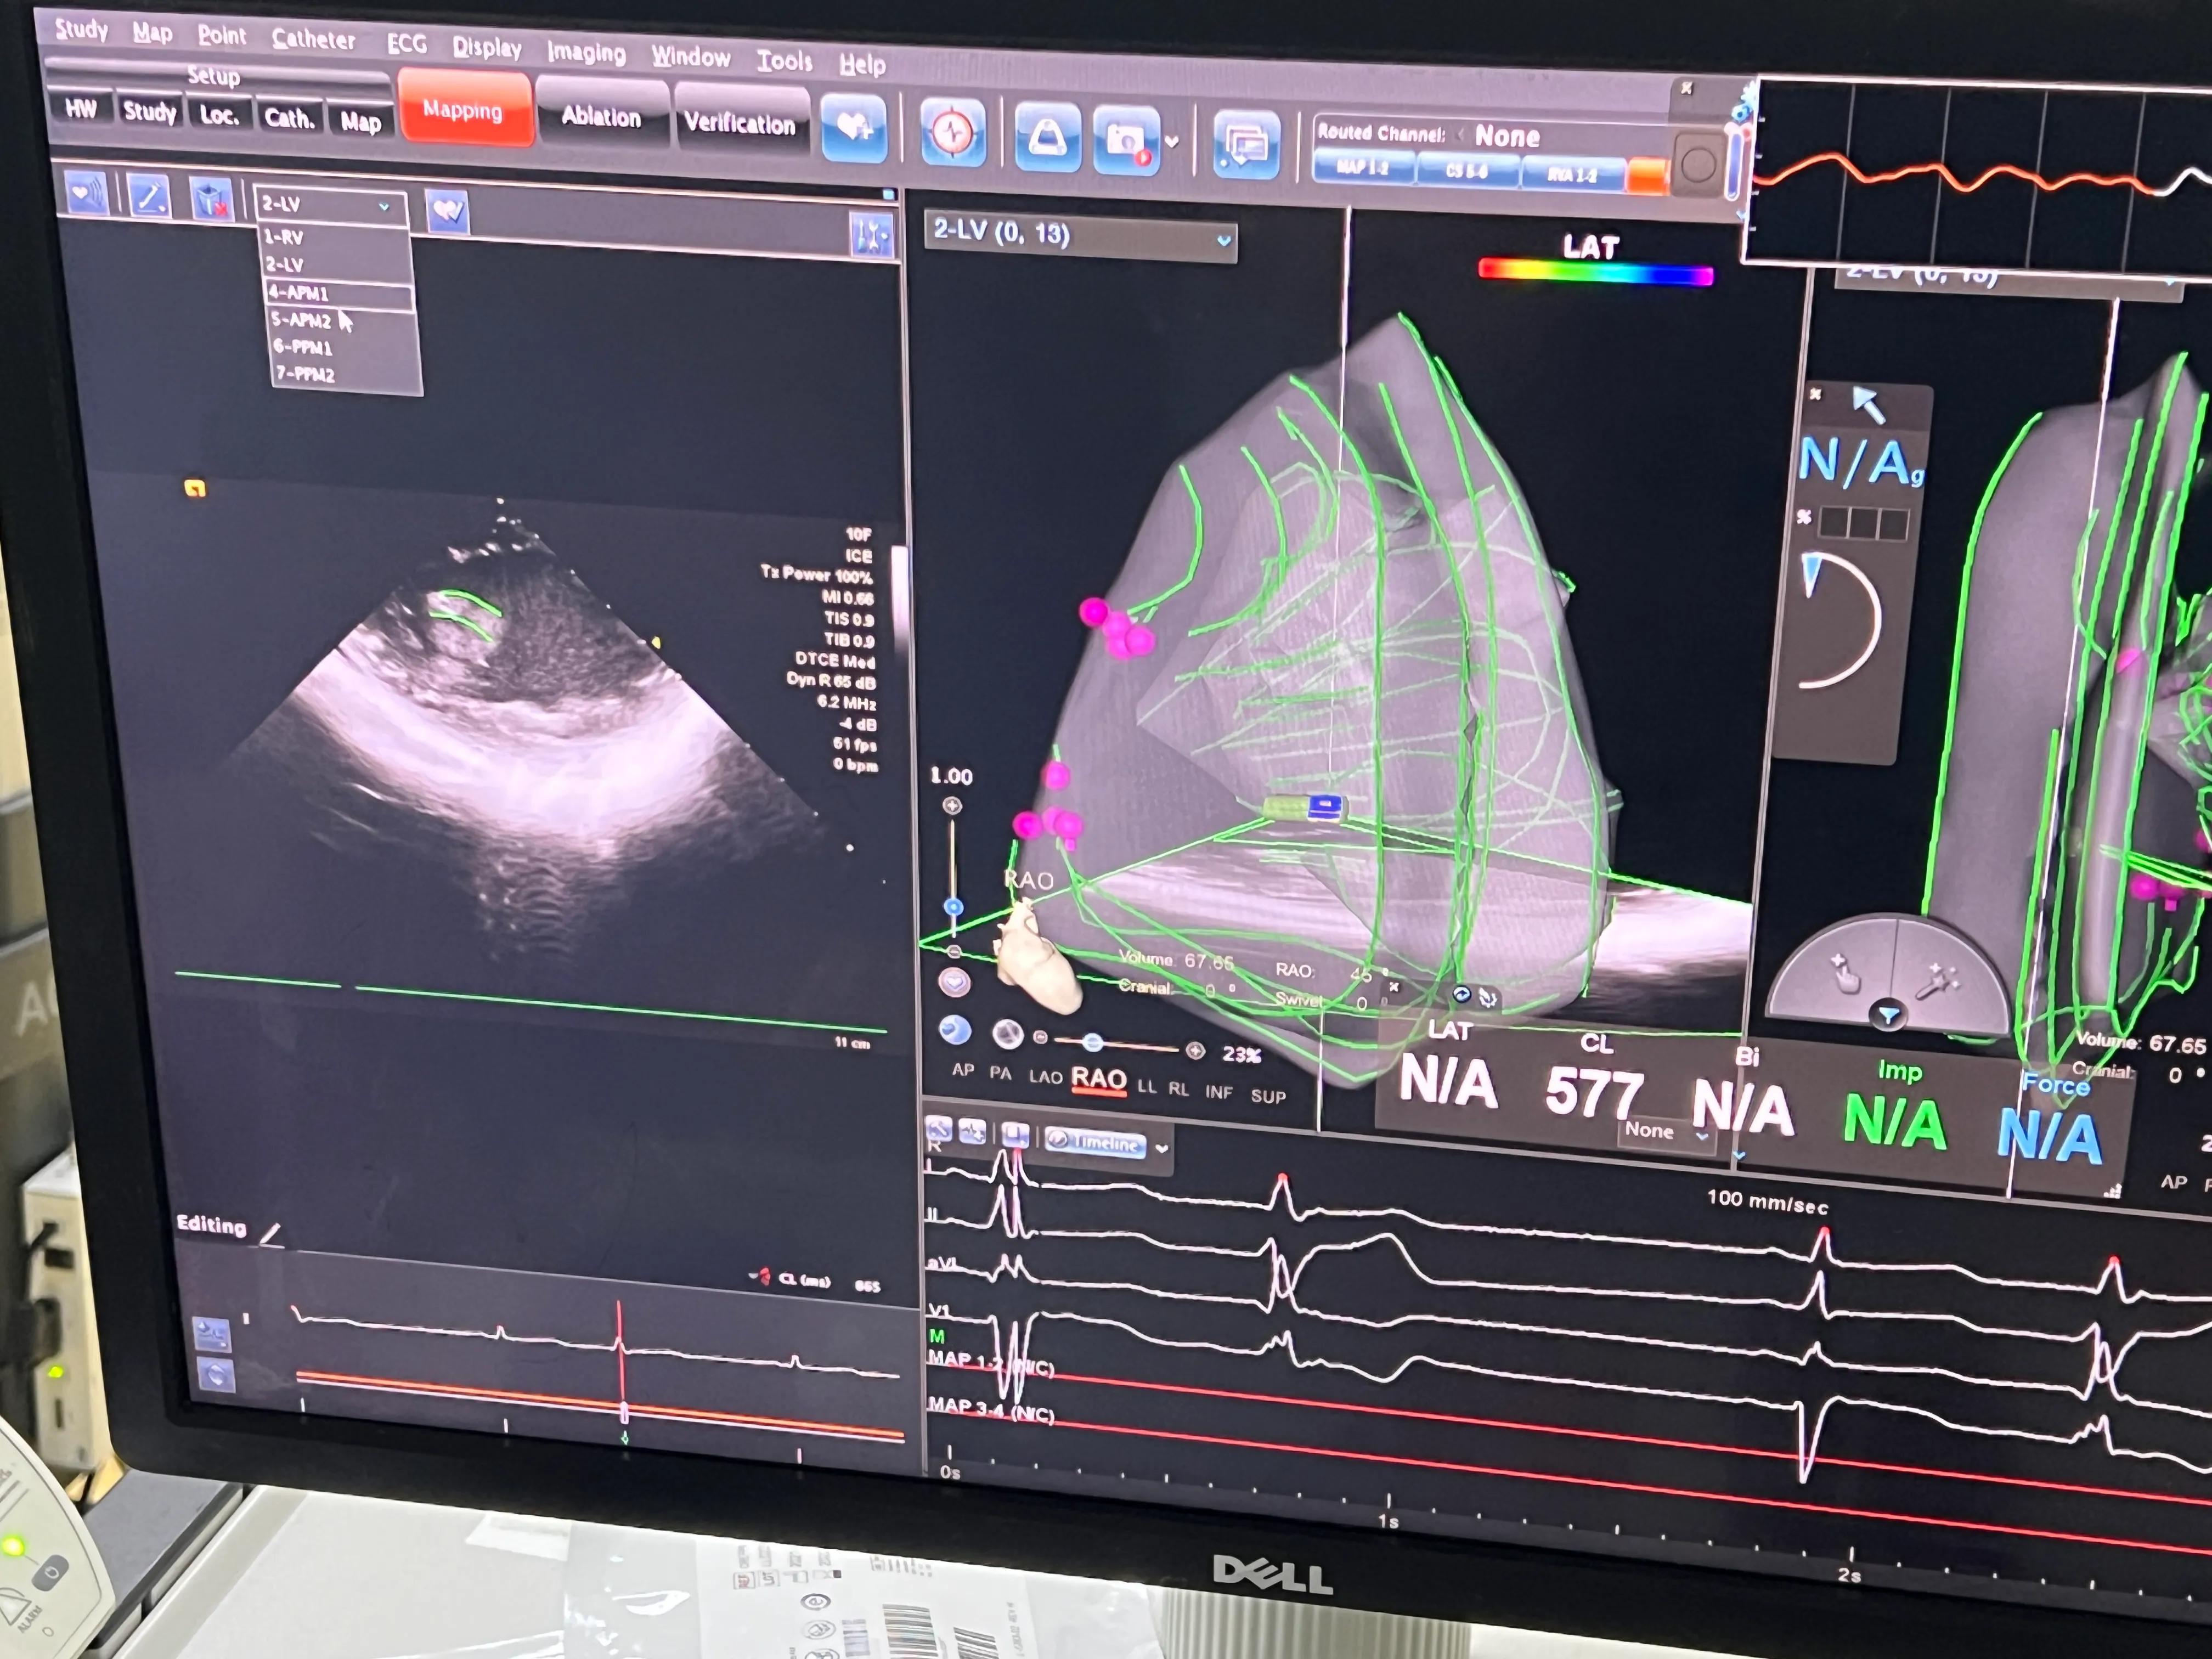

上手术台心电监护提示频发室早二联律,从体表心电图,考虑左后乳头肌室早可能,穿刺右侧股静脉和股动脉各1支。然后送入Soundstar超声建模

图3:三维超声建模左室及乳头肌